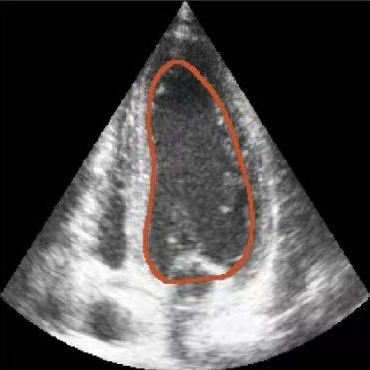

Figure 1: Illustrative challenges for echocardiography video segmentation: (a) speckle noise, (b) indistinct or blurred contours, and (c-f) the substantial changes in the target’s shape and scale throughout the cardiac cycle.

However, achieving precise segmentation in echocardiography faces severe challenges stemming from poor image quality and complex cardiac dynamics. Figures 1(a) and 1(b) show that ultrasound images are characterized by high speckle noise and low contrast, which obscure tissue structures and lead to weak or incomplete anatomical boundaries. These artifacts hinder the model’s ability to learn robust features and can result in the inaccurate segmentation. In the temporal dimension, the heart undergoes significant non-rigid deformation throughout the cardiac cycle. Figures 1(c), 1(d), 1(e) and 1(f) show that, the shape and scale of the LV change dramatically between systole and diastole. This substantial dynamic variation demands that segmentation models possess strong temporal modeling capabilities to accurately track the changing appearance of the target across the video sequence [20].